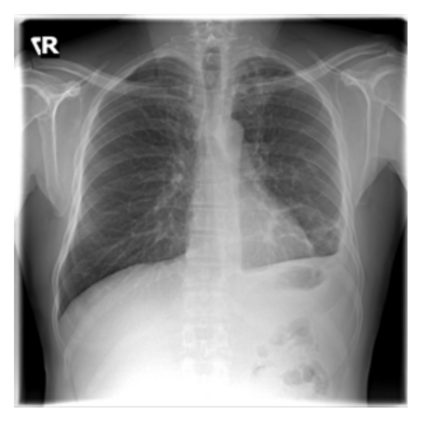

The evaluation of infectious disease processes on radiologic images is an important and challenging task in medical image analysis. Pulmonary infections can often be best imaged and evaluated through computed tomography (CT) scans, which are often not available in low-resource environments and difficult to obtain for critically ill patients. On the other hand, X-ray, a different type of imaging procedure, is inexpensive, often available at the bedside and more widely available, but offers a simpler, two dimensional image. We show that by relying on a model that learns to generate CT images from X-rays synthetically, we can improve the automatic disease classification accuracy and provide clinicians with a different look at the pulmonary disease process. Specifically, we investigate Tuberculosis (TB), a deadly bacterial infectious disease that predominantly affects the lungs, but also other organ systems. We show that relying on synthetically generated CT improves TB identification by 7.50% and distinguishes TB properties up to 12.16% better than the X-ray baseline.